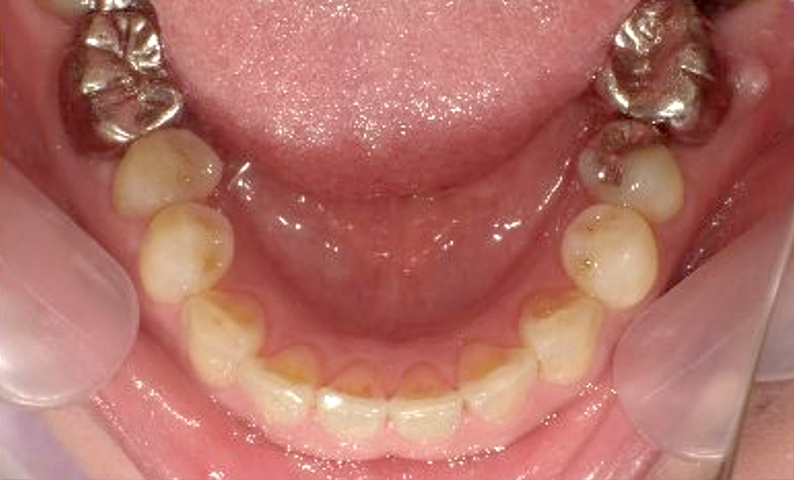

症例_030 上下顎の部分矯正

治療期間:12ヶ月金額:54万円+税女性八の字/V字型捻転歯前歯のガタガタ

| Before | After |

|---|---|

|